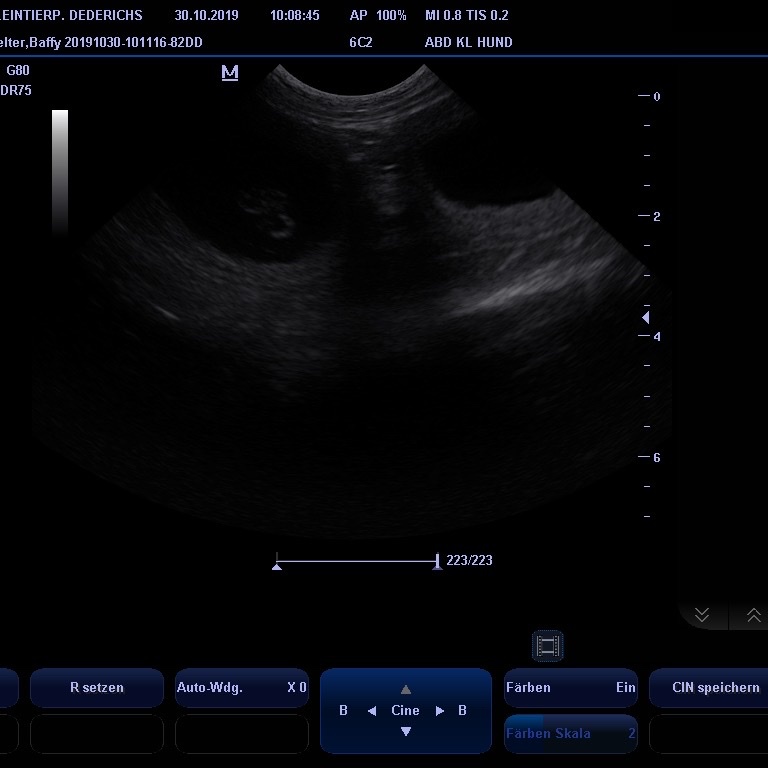

am 29.09. 2019 ist Baffy zu dem Vater des J-Wurfes Jakito von Falkensee gefahren. Kaum angekommen haben die Zwei beschlossen sich zu "lieben"